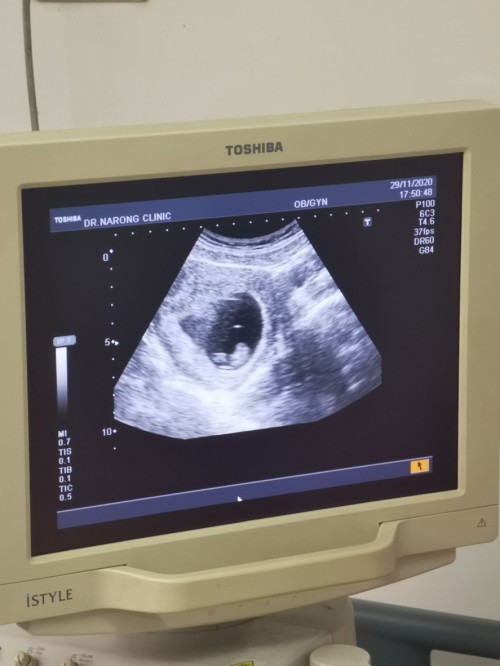

30 มิ.ย 64 จร้า 🥰🥰🥰 หัวใจเต้นตุ๊บๆแล้ว

9 มิ.ย จ้า เห็น น้องกับหัวใจเต้นแล้ว

เต้นแล้วจ้า บ้านนี้กำหนดคลอด 6 มิถุนา

14 มิ.ย ค่า ซาวน์เจอหัวใจเต้นตอน 6wk3d